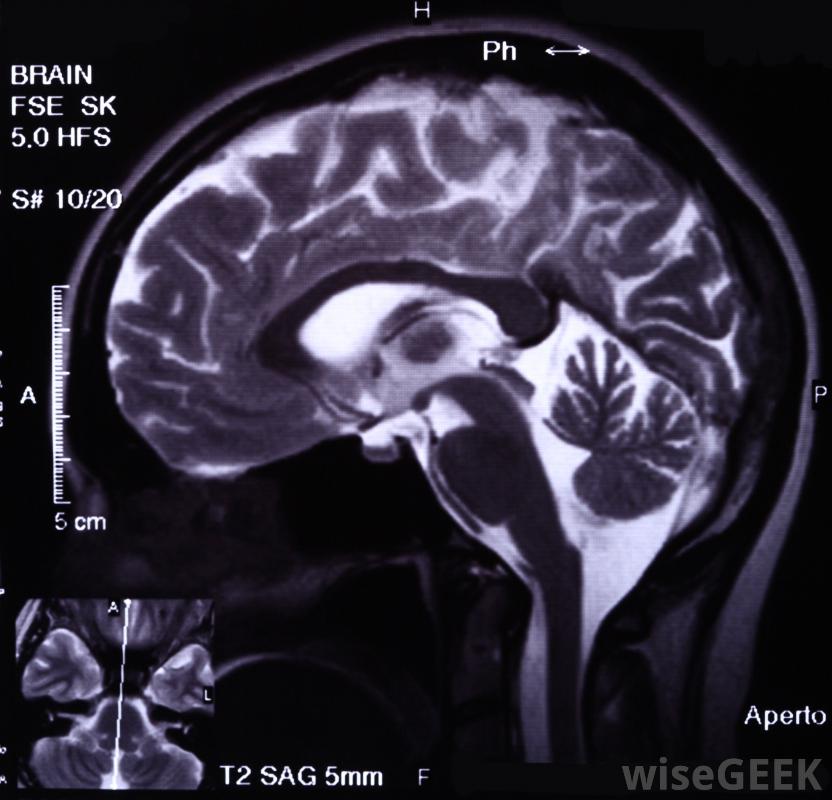

医生可能会建议对癫痫患者进行脑电图扫描先兆过后,一个人通常会显得空虚,可能会进行奇怪的、重复性的身体动作,例如拍打嘴唇或咀嚼。几秒钟或几分钟后,癫痫发作结束,随后出现一段持续数分钟的混乱期。有时,在意识丧失的复杂部分癫痫发作中,癫痫发作并没有结束,而是发展成一种全身性的癫痫。精神运动性癫痫可以通过核磁共振成像、扫描和脑电图或记录大脑电活动的脑电图来诊断。对大多数人来说,癫痫发作可以通过药物控制小发作性癫痫可以用药物治疗。

脑部核磁共振成像可能有助于精神运动性癫痫的诊断